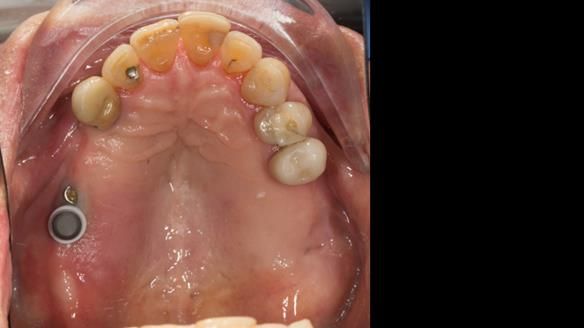

The upper jaw

In the upper arch:

- a failing upper left tooth supporting a bridge was removed

- an implant-supported bridge on the upper right was dismantled

A metal-based upper RPD was made,

with metal backings incorporated to future-proof the design

should further teeth fail.